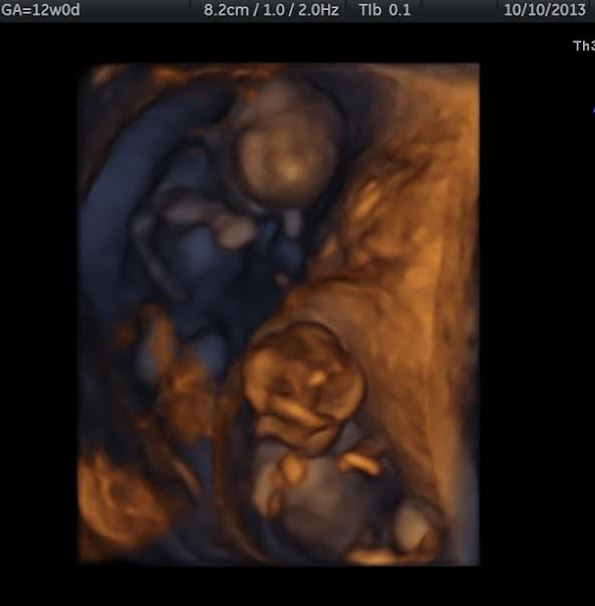

9dp5dt Beta 1 = 344!! 16dp5dt. Beta 2 = 4822 7wk u/s= 2 heartbeats!